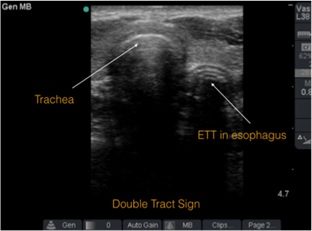

Entonces, al pasar el tubo tenemos 2 opciones, que esté en tráquea o en esófago. Vamos a ver cómo se ven ambas situaciones a la ecografía:

- Cuando el tubo está en la tráquea, se debería ver una segunda estructura hiperecoica adentro de la tráquea. El esófago –siendo una cavidad que basalmente está colapsada- se debería ver sin ningún cambio (figura 2).

- Cuando el tubo está en el esófago, la tráquea se va a ver sin cambios, pero donde está el esófago, se verá una segunda estructura que se verá como una segunda tráquea, incluso con cola de cometa (figura 3).